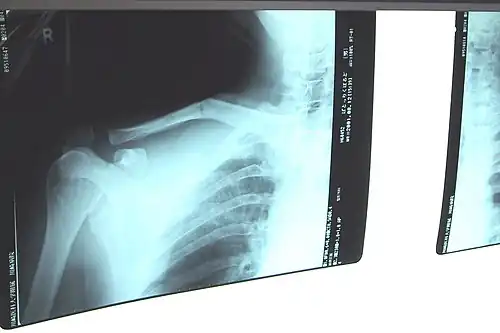

Il est radiographique affirmé par la radiographie de face. Idéalement il s'agit d'un cliché « clavicule de face » ascendant à 30° sur l'horizontale qui visualise mieux l'os et le foyer. Le fragment proximal est habituellement déplacé vers le haut en raison de la traction du muscle sterno-cléido-mastoïdien, le fragment distal étant attiré vers le bas par le poids de l'épaule et la traction du muscle deltoïde. Il se produit un raccourcissement par perte de l'arc boutant claviculaire avec un déplacement du moignon de l'épaule vers la ligne médiane.

D'un homme de 26 ans .

Sc: banque photo institut québécoise de radiologie [1]